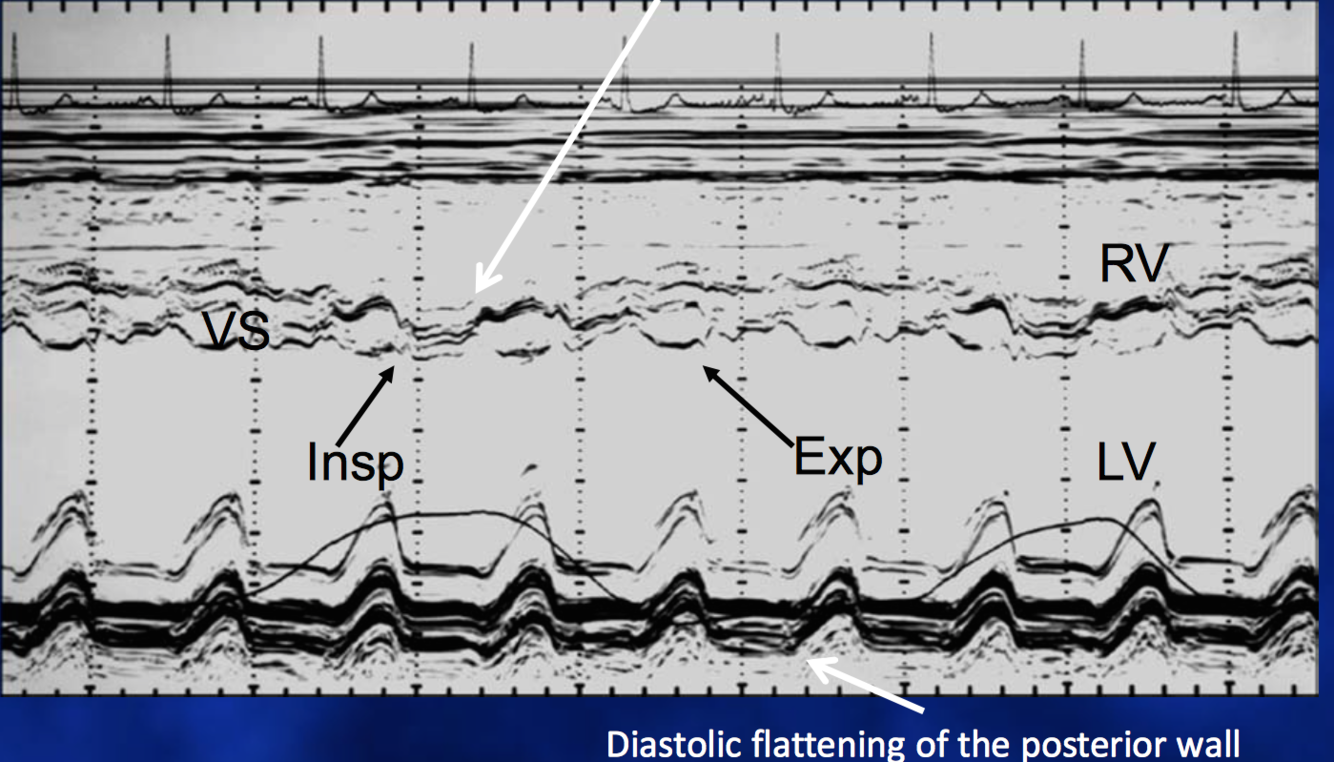

Diagnosis?

Constrictive Pericarditis (left shift of interventricular septum during inspiration)

Tamponade

(interventricular interdependence, see how the septum moves away from RV and dips towards LV on inspiration)